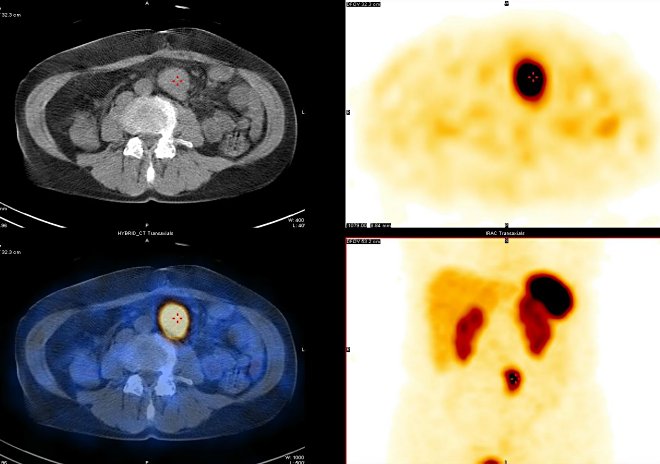

Obr. 2: SPECT, CT a SPECT/CT dutiny břišní, transverzální řezy.

/ Obr. 2: SPECT, CT a SPECT/CT dutiny břišní, transverzální řezy. /

Zobrazila se lymfatická uzlina (35 x 31 x 30 mm) s patologicky zvýšenou koncentrací somatostatinových receptorů v karcinoidu ve středním retroperitoneu paraaortálně vlevo. Jinde nebylo zastiženo ložisko tkáně s patologicky zvýšenou koncentrací somatostatinových receptorů. Závěr: metastáza karcinoidu v lymfatické uzlině ve středním retroperitoneu paraaortálně vlevo s vysokou koncentrací somatostatinových receptorů.